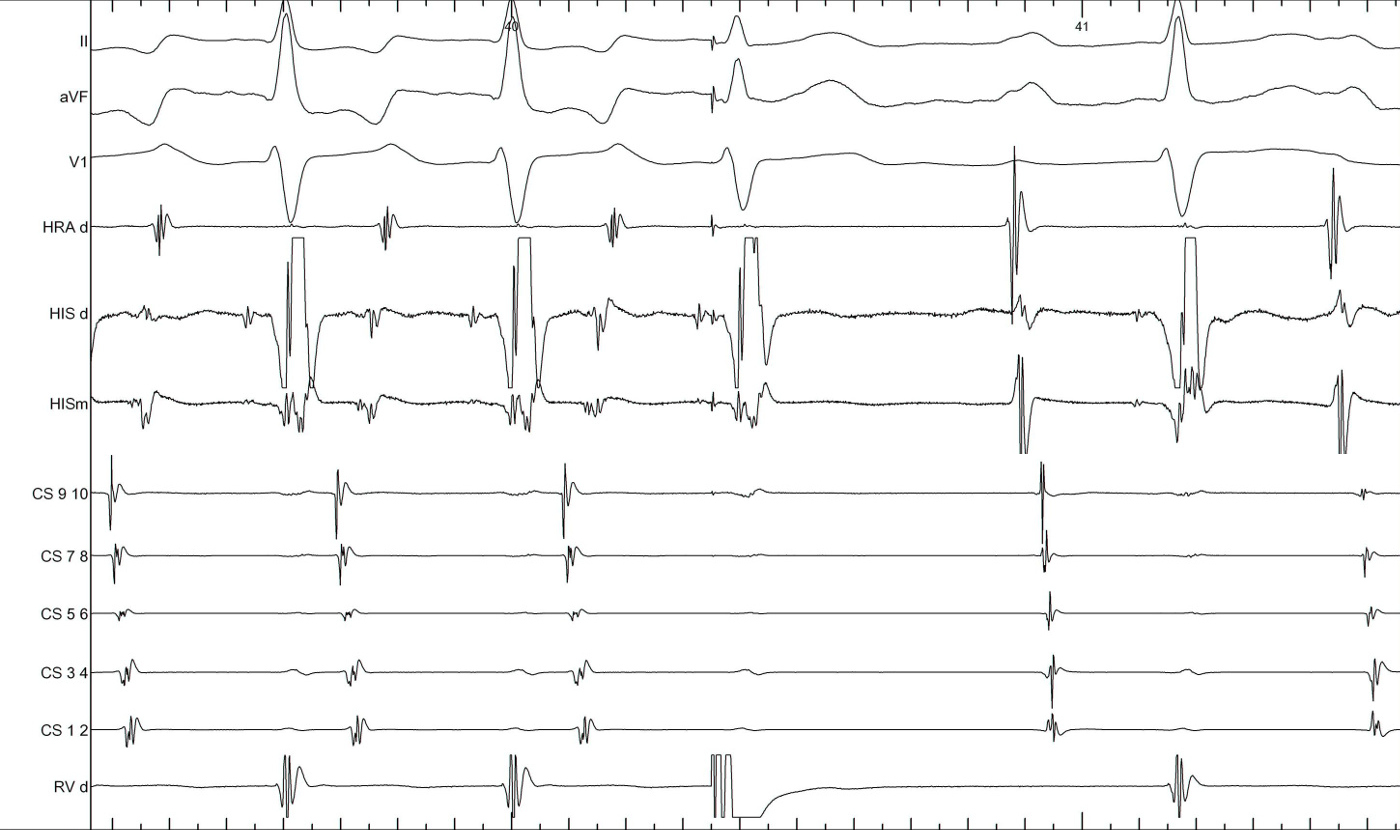

Other clues during narrow QRS tachycardia

• VA unlinking - spontaneous or after atrial burst

• Cycle length and VA changes with bundle branch block

• Spontaneous termination

Bundle branch block

lbbb_narrow.jpg

lbbb_narrow_measurements.jpg

coumel.jpg